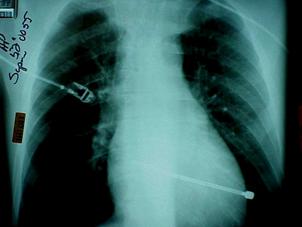

Contuzie pulmonara stanga Contuzie pulmonara dreapta

Contuzie pulmonara dreapta.Imagine CT

Ruptura de trahee